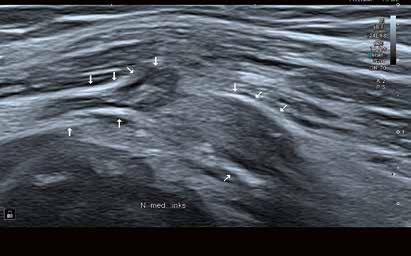

60 Ein Plädoyer für hochwertige Ultraschallausrüstung in der neurologischen Praxis

ULTRASCHALL

68 Traumatische Nervenläsionen –über den Einsatz des Nervenultraschalls

Create a flipbook

Issuu converts static files into: digital portfolios, online yearbooks, online catalogs, digital photo albums and more. Sign up and create your flipbook.